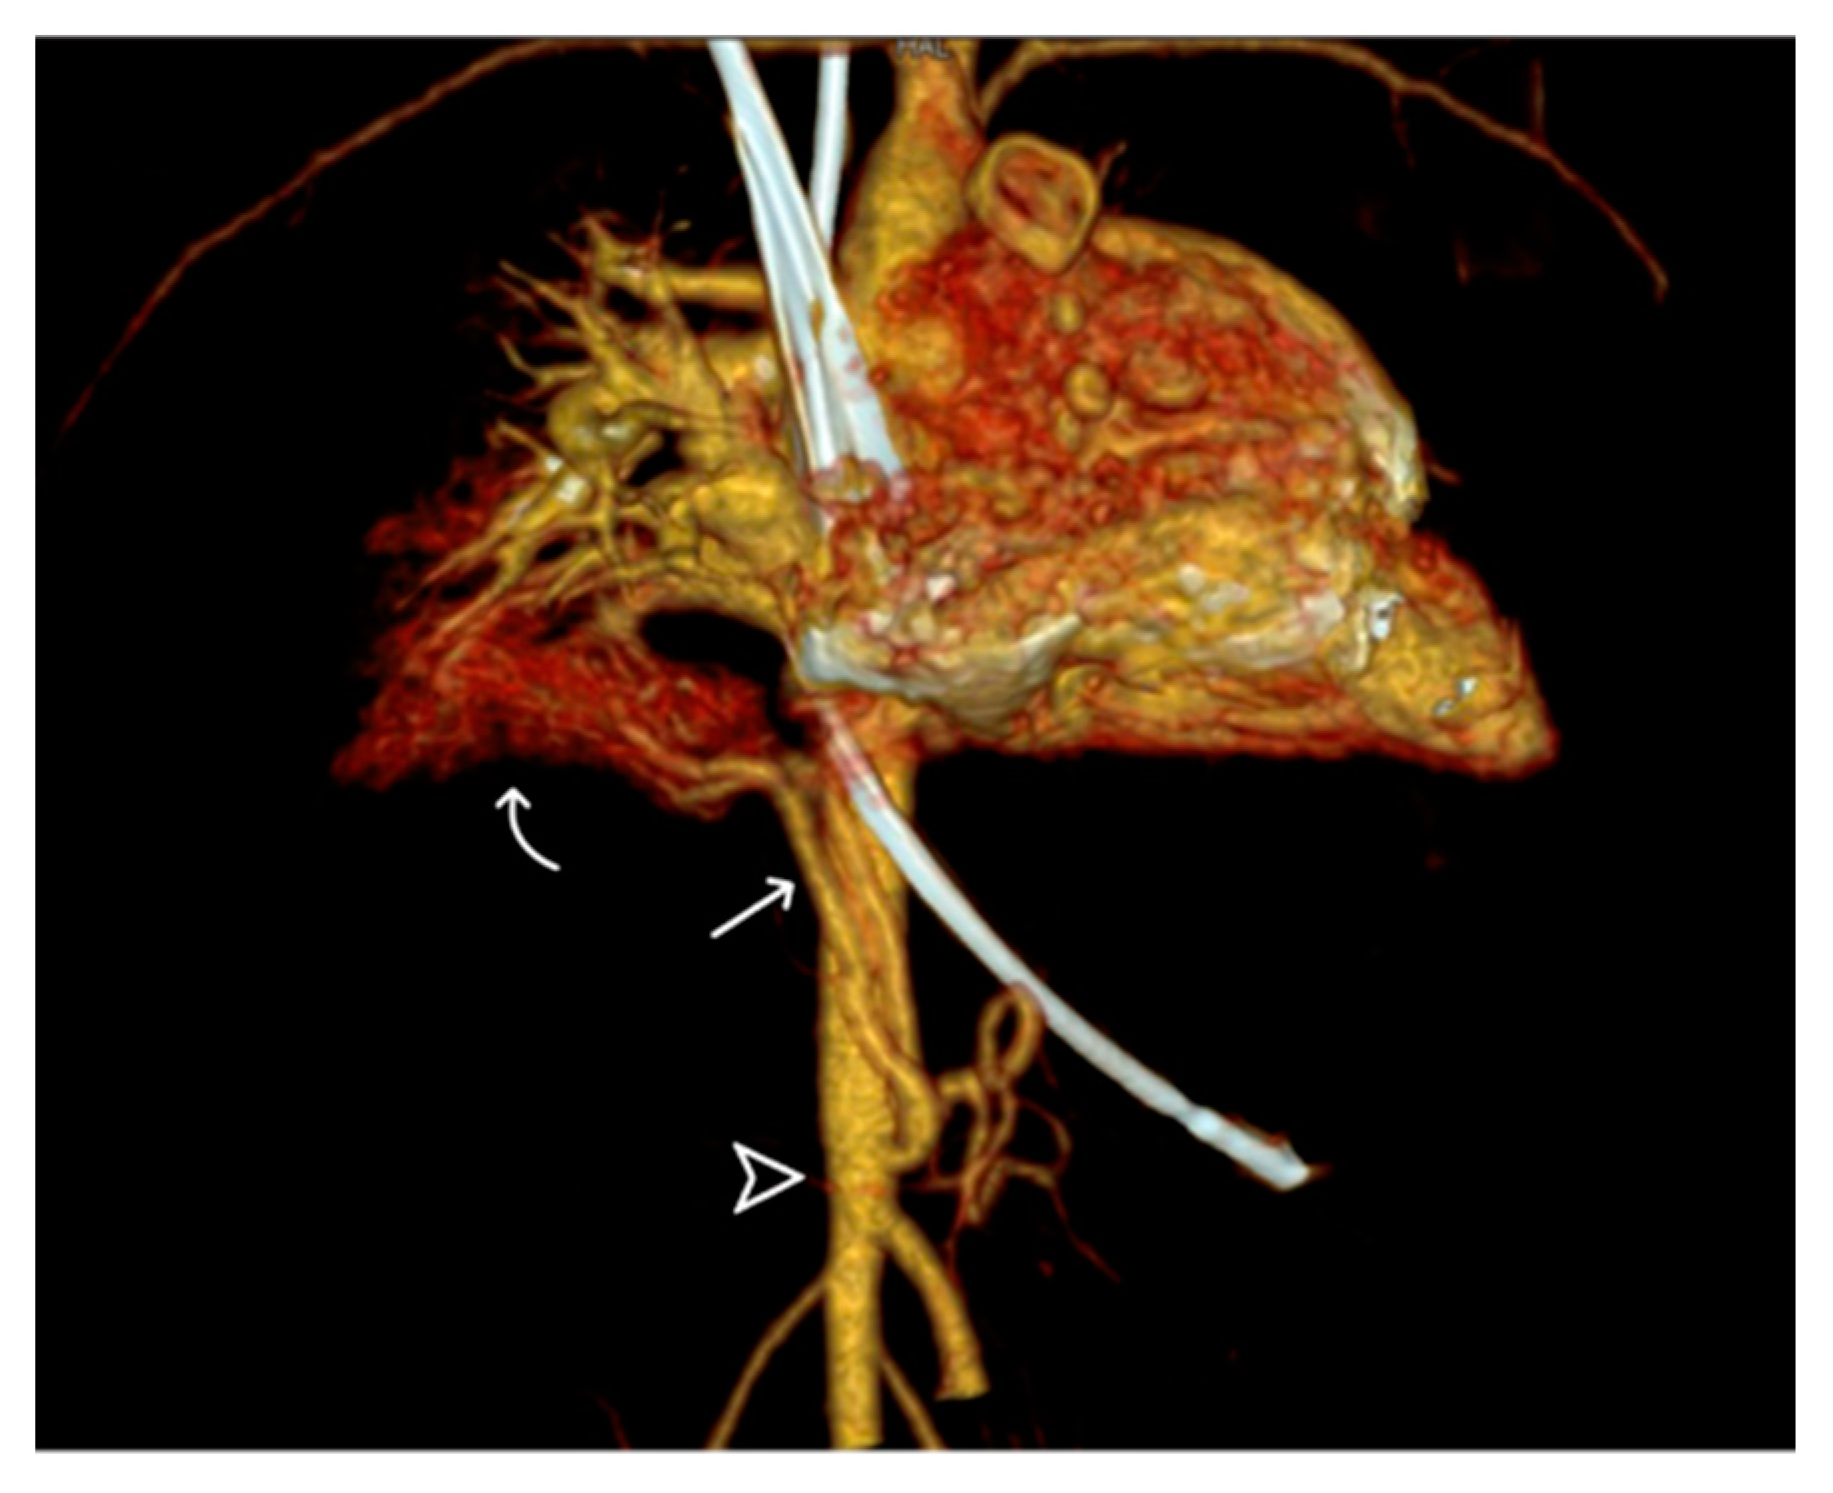

Figure 5.

Volume-rendering 3D reconstructive image displaying the anterior aberrant systemic artery (arrow) from the descending abdominal aorta (arrowhead), forming a vessel sponge in the right basal lung (curve arrow).